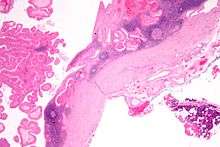

Histopathology of Warthin tumor in the parotid gland. H&E stain.